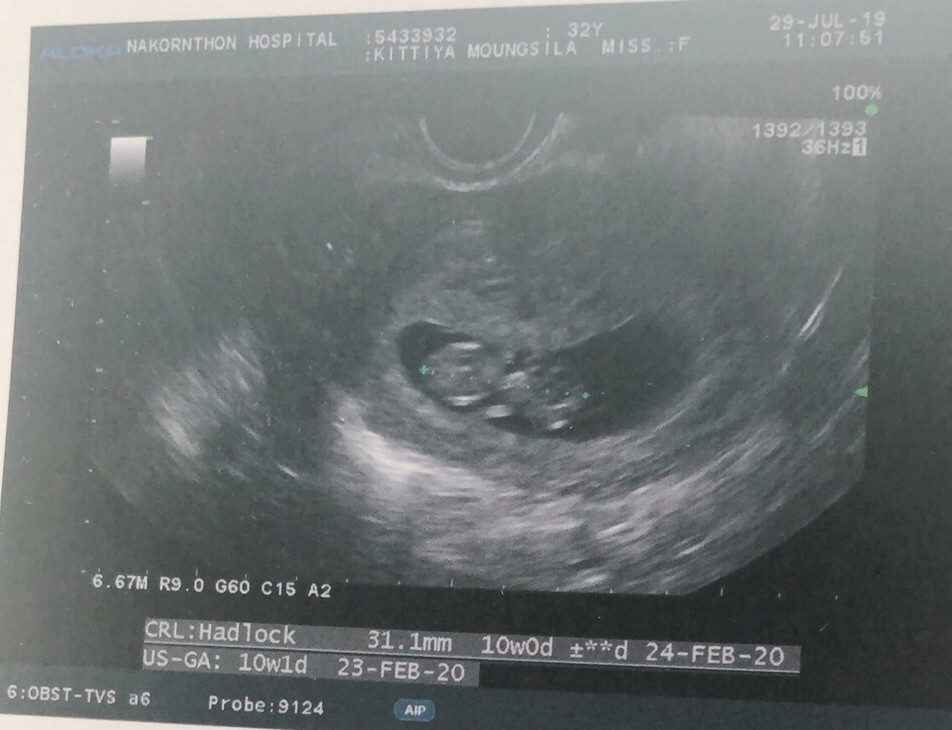

10.weekพอดีเป๊ะค่ะ